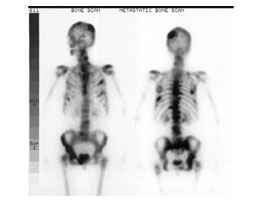

View Bone Scan Images Showing Cancer Images. It is a useful tool for finding cancer a bone scan is a nuclear medicine test. Bone scans can show if a cancer has spread to other bones.

I used google images to check this out and some spots that looked to me like cancer were actually old breaks or injuries. Imaging in cancer diagnosis can be a beneficial tool to detect malignancies at their earliest stages to increase these help your doctor look for cancer in various areas of your body, including your organs like your kidneys and stomach and bones. Scan b shows numerous bone hot spots, a result of cancer that has spread to multiple locations.